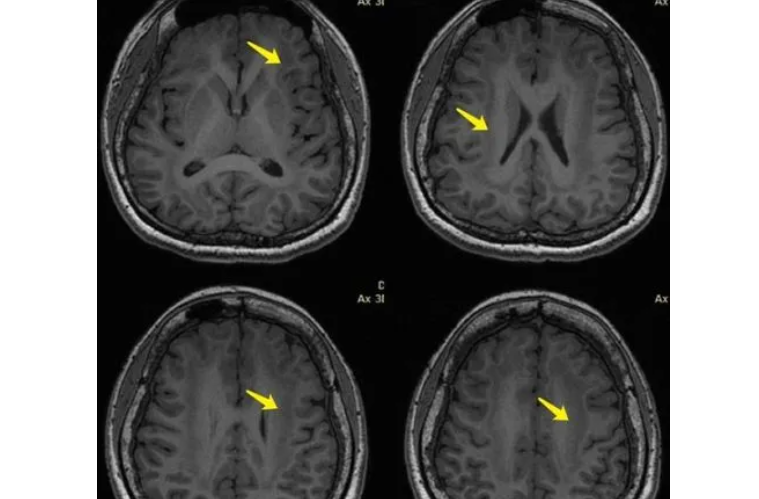

脑多发缺血灶是指大脑多个部位出现缺血性病变的疾病,也被称为多发性脑缺血病。它是一种常见的脑血管疾病,严重影响患者的生活和健康,甚至可导致残疾和死亡。脑多发缺血灶引起的症状多样化,包括头痛、头晕、记忆力减退、肢体无力等。

脑多发缺血灶的症状多样化,常见的症状包括头痛、头晕、失眠、记忆力减退、注意力不集中、思维迟缓、情绪波动和肢体无力等。一些患者还可能出现言语困难、行走不稳、视力模糊等症状。这些症状会对患者的生活产生严重影响,甚至会导致脑卒中等并发症的发生。